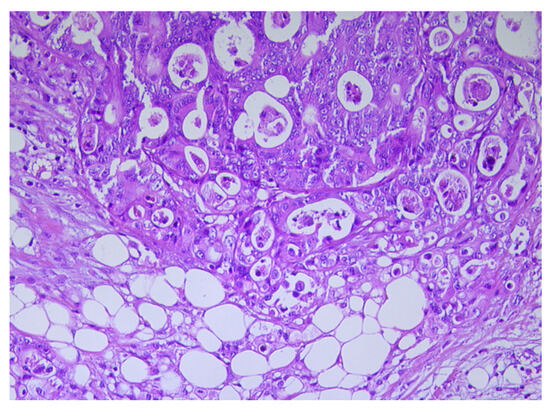

2. The Crosslink between Obesity and Colorectal Cancer

3. Cancer-Associated Adipocytes (CAAs) Characteristics

4. Potential Mechanisms of CAAs Differentiation in CRC